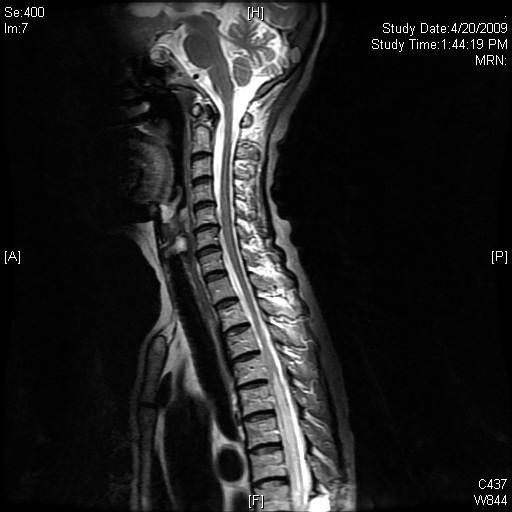

Ten days later, the patient complained of bilateral upper limb weakness and paresthesia. Sensory level had progressed to about T7. MRI of the spine now showed interval worsening of abnormal spinal cord enhancement and swelling to T4 level to the conus medullaris and new involvement of the cervical cord (Fig. 3). As no definite explanation could be given for the progression of spinal cord abnormality, a cord biopsy was performed. This showed extensive spinal cord necrosis with no tumour involvement. There was no evidence of thrombosis or inflammation of the spinal vessels. CSF obtained intraoperatively was again negative for infection and malignancy.

![]() Click for large image | Figure 3. (a) MRI of the spine showing cord edema progressing cranially to involve the cervical spine. (b) MRI demonstrated edema involving the conus medullaris. |